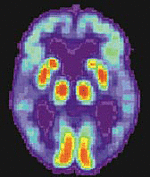

Positronen-Emissionstomografie eines Alzheimer-Patienten